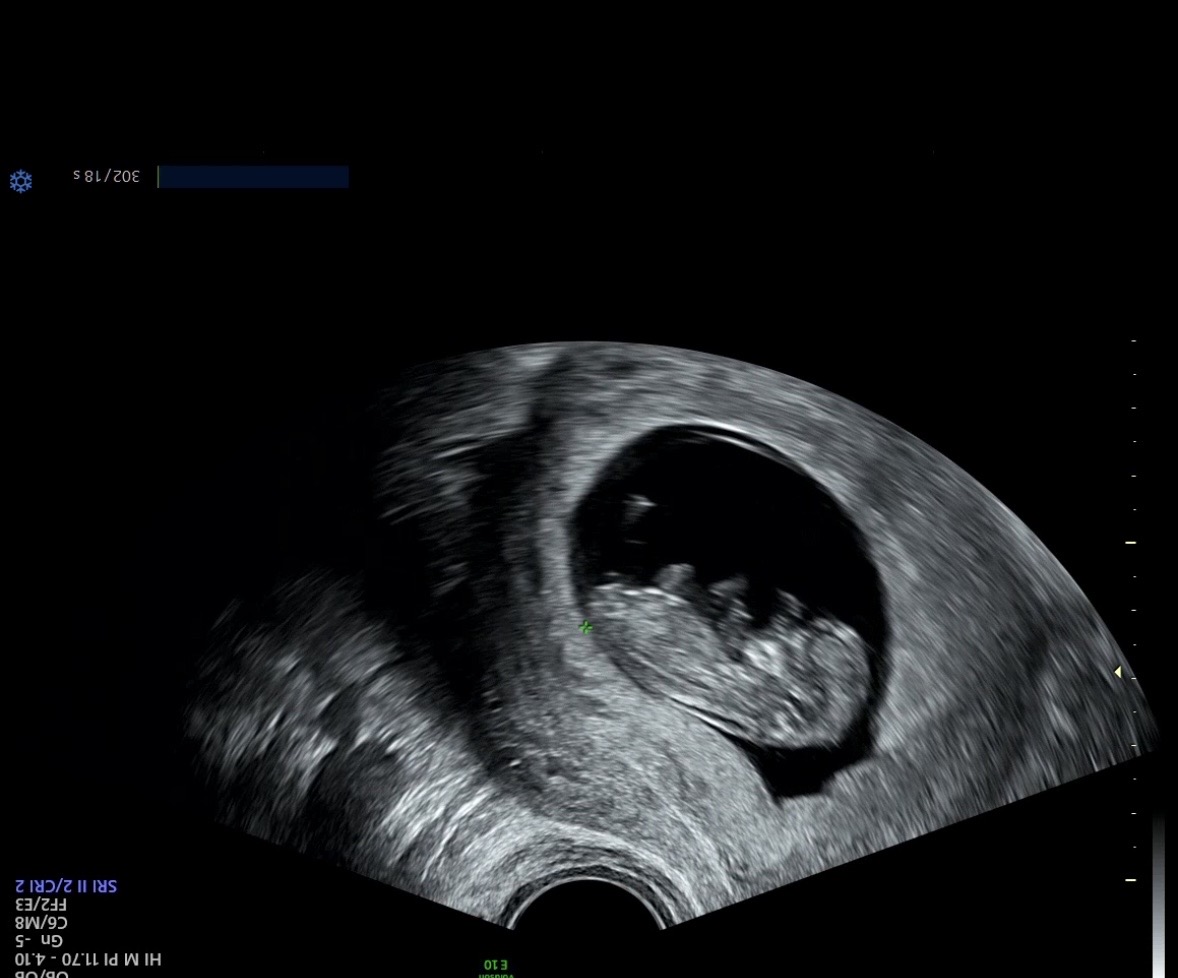

10주차 … 아직 아무것도 모르는 시기지만 .. 고수님들 .. 그냥 예상만이라도 부탁드려요오~~ㅎㅎ